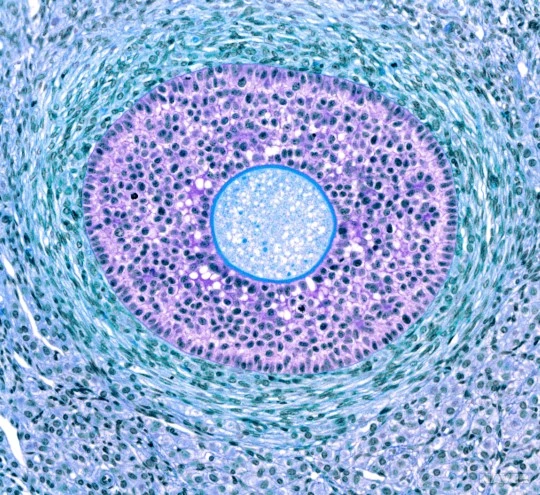

성숙여포(mature follicle, Graafian follicle): 2차여포의 성장에 따라 여포동도 커지는데, 일차난모세포가 있는 부분의 과립층세포는 난포세포더미인 난구(cumulus oophorus)를 형성한다. 배란시 난모세포를 둘러싸고 같이 배출되는 난구의 세포들을 방사관(corona radiata)이라 한다. 성숙난포는 직경이 10 mm이상으로 피질 전체에 걸쳐 있고 난소표면으로 융기되어 있다. 배란 24시간 전에 황체형성호르몬(leteinizing hormone, LH)의 분비가 급격하게 증가하여 일차난모세포의 일차감수분열이 시작되고 이 결과 이차난모세포와 제1극체가 형성된다. 매달 한 개의 성숙난포가 우세여포(dorminant follicle)로 되어 배란되며, 나머지 대부분의 발달 중인 여포는 발달을 멈추고 난포 패쇄(atresia)인 세포자살(apoptosis) 과정을 통해 퇴화하게 된다.

난소의 구조 및 난포 종류(출처: 한국통합생물학회)

후기일차난포의 광학현미경 사진(출처: GettyimagesKorea)